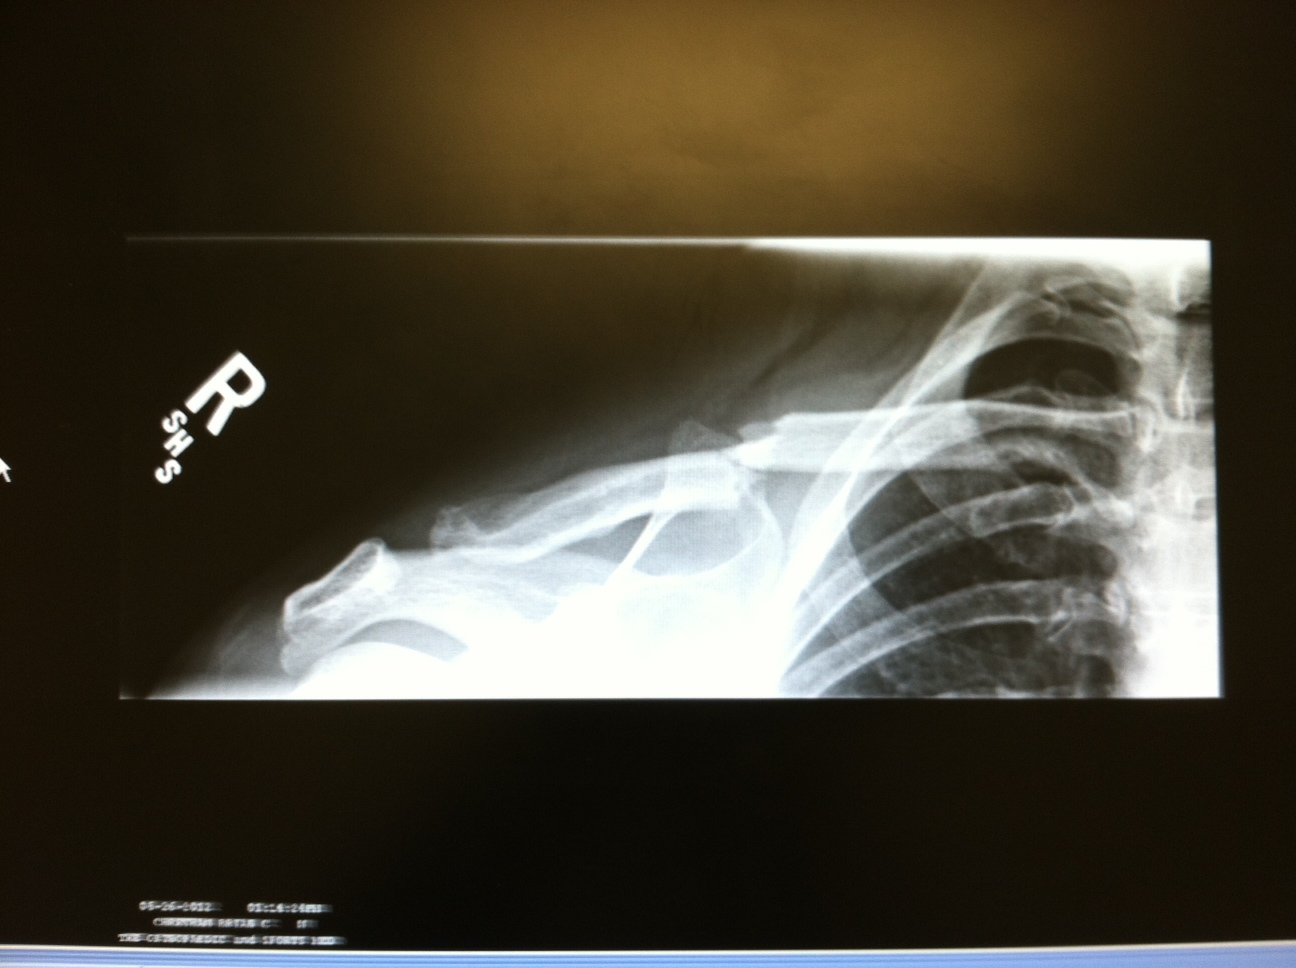

Broken Collarbone X-Ray Bone healing usually takes 3 to 6 weeks for children. To learn more about the severity of the break; People who have a broken collarbone usually need to wear a sling. Bone healing usually takes 3 to 6 weeks for children. If the bone isn't too out of place and didn't break through the skin, you might be treated with a sling and limited. To help pinpoint the location of the fracture; A broken collarbone is a fracture in one of your clavicles: The clavicle is the most proximal bone of the upper. The two slender bones that start from the top of your sternum and extend. Clavicle fractures result in inferior displacement of the distal component. Symptoms of a broken collarbone include severe pain and swelling at the site of the fracture and with visible. The clavicle (collarbone) is one of the most fractured bones in the body.

From www.podiumcafe.com